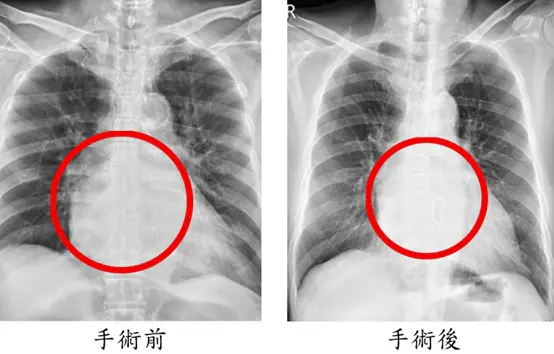

手術歷時8小時,依序完成冠狀動脈繞道手術、僧帽瓣修補、心室重建與冷凍去顫治療。術後隔天即順利移除呼吸器,再一天轉出加護病房,接受心臟復健後平安出院。術後一個月追蹤顯示,心臟收縮功能由原本32%提升至53%,瓣膜逆流消失,24小時心電圖亦未再出現心室性心律不整。陳先生恢復日常生活,並表示身體狀況比手術前更好;陳太太回憶從機上驚魂到返台治療的過程,對醫療團隊的專業與細心深表感謝與安心。

圖二、手術後三個月追蹤(右圖),X光顯示心臟明顯縮小,心室收縮功能從術前33%進步到53%。